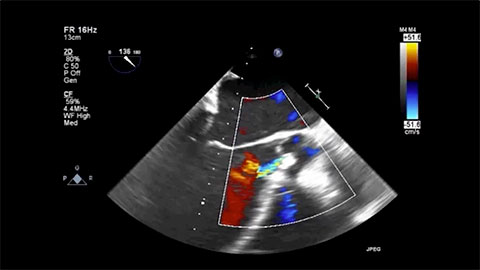

De-Airing & Initiating Pump Operation

This video describes how to de-air and initiate pump operation for the HeartMate 3 LVAD.